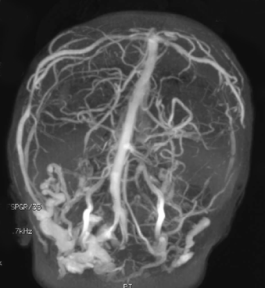

il existe une HTIC en raison de la compression cérébrale, mais aussi des sinus veineux (Cf. ci-contre) surtout si les sutures lambdoïdes sont également fermées.

- l’IRM montre la compression cérébrale, la compression des sinus veineux et la circulation de suppléance par les veines trans-osseuses, l’engagement tonsillaire